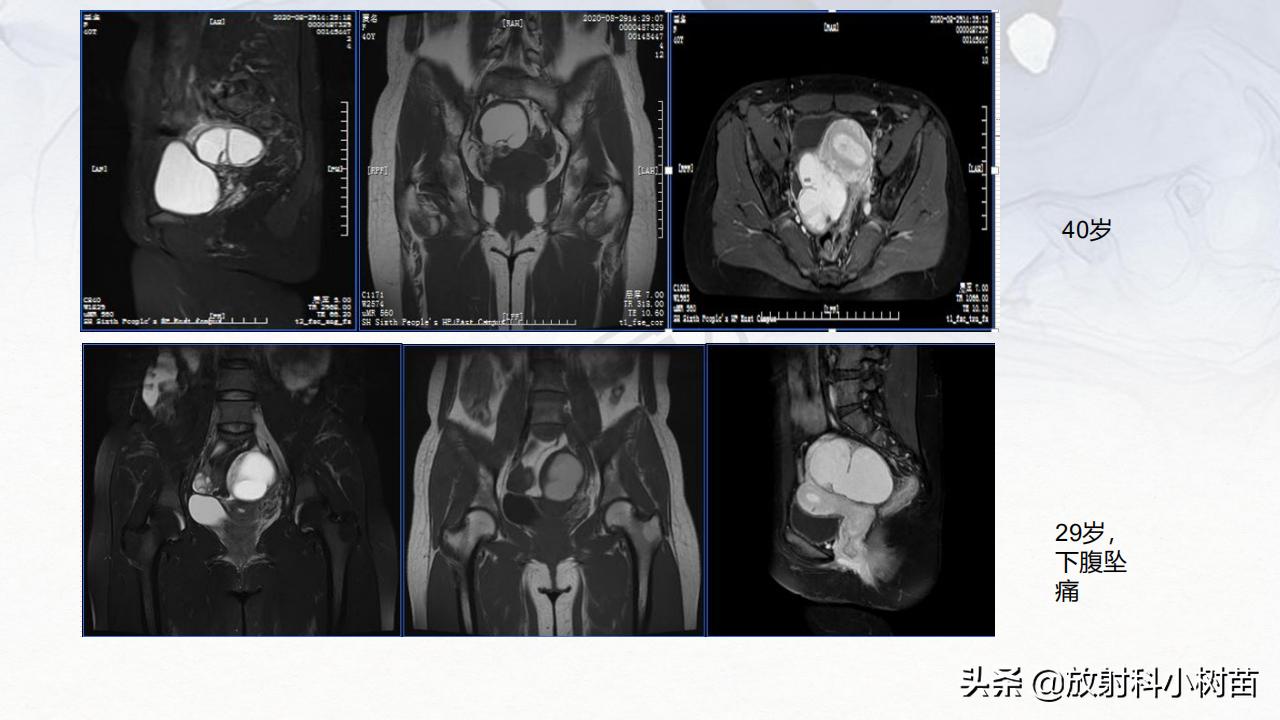

子宫体:肌层?(腺肌症,肌瘤,肉瘤),内膜?(增生,息肉、内膜癌)